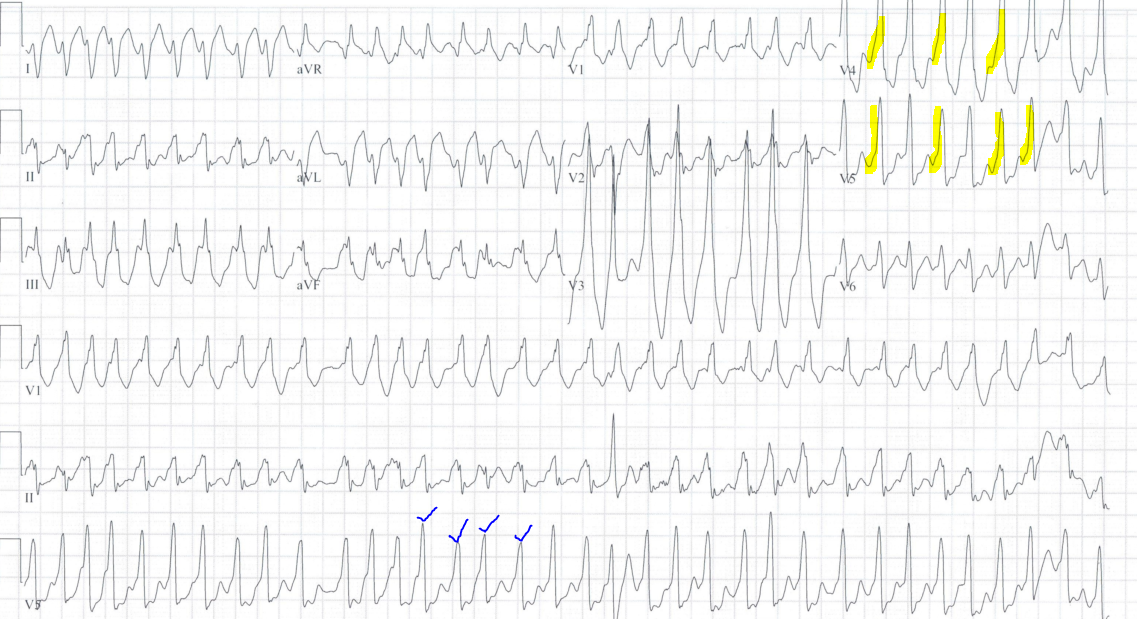

Atrial fibrillation in a patient with Wolff-Parkinson-White

-Irregularly irregular tachycardia with no clear P waves

-Close inspection of the QRS complexes reveals variation in the morphology from beat to beat in the same lead (blue checkmarks)

-Notice the slow upstroke, particularly in V4 and V5 consistent with the delta wave seen in WPW (yellow highlight)